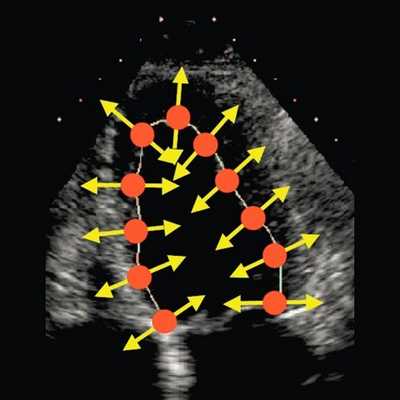

В настоящее время бурное развитие современных ультразвуковых технологий привело к появлению совершенно иных подходов к оценке функционального состояния сердца, которые на очень ранних этапах заболевания позволяют выявлять минимальные нарушения функции сердца. Мы еще не успели должным образом изучить возможности тканевой допплерографии, как появилась еще одна методика, получившая в англоязычной литературе название - speckle tracking. В отличие от тканевой допплерографии, основанной на эффекте допплера, speckle tracking основан на определении скорости движения миокарда при помощи отслеживания перемещения естественных акустических маркеров - пятнистых структур, на стандартном эхокардиографическом изображении в В-режиме (рис. 1).

![Эхограмма (В-режим) - оценка скорости движения миокарда, отслеживание перемещения естественных акустических маркеров - пятнистых структур]()

Рис. 1. Оценка скорости движения миокарда при помощи отслеживания перемещения естественных акустических маркеров - пятнистых структур, на стандартном эхокардиографическом изображении в В-режиме.

Суть метода заключается в том, что акустические маркеры случайным образом равномерно распределяются по всему миокарду. Размер каждого пятна составляет от 20 до 40 пикселей (точек). Положение каждого пятна определяется и точно прослеживается на последовательных кадрах. Таким образом, можно определить расстояние, на которое перемещается пятно от кадра к кадру. Зная частоту смены кадров, можно определить скорость движения пятна. С целью повышения качества отслеживания пятнистых структур применяется высокая частота смены кадров - 60-100 кадров в секунду. Особенности движения сердца, вращение в грудной клетке, а также дыхательная экскурсия грудной клетки могут приводить к смещению пятен из плоскости сканирования. Однако эти изменения не успевают произойти в значимом количестве между двумя последовательными кадрами. Таким образом, по движению пятнистых структур можно получить данные о скорости, деформации и скорости деформации всех участков миокарда. Техника вычисления деформации по двухмерному изображению значительно проще, чем при использовании тканевой допплерографии, так как при этом отсутствуют ограничения, связанные с параллельностью движения объекта и ультразвукового луча. Для последующих вычислений достаточно одного сердечного цикла (рис. 2). Обработка ультразвуковых изображений проводится в режиме offline [2].

![Эхограмма (В-режим) - оценка продольной деформации левого желудочка, технология speckle tracking]()

Рис. 2. Оценка продольной деформации левого желудочка с помощью ультразвуковой технологии speckle tracking в В-режиме.

С появлением ультразвуковой технологии speckle tracking стало возможным более детальное изучение регионарной систолической и диастолической функции не только продольных волокон, но и радиальных, окружностных, поскольку, новая технология лишена угловых ограничений, присущих тканевой допплерографии. Это делает возможным исследование продольной сократимости даже верхушечных сегментов левого желудочка. Благодаря технологии speckle tracking стало возможным изучение показателей апикальной и базальной ротации, скручивания и раскручивания сердца, что позволяет по-новому оценивать физиологию сокращения и расслабления миокарда.